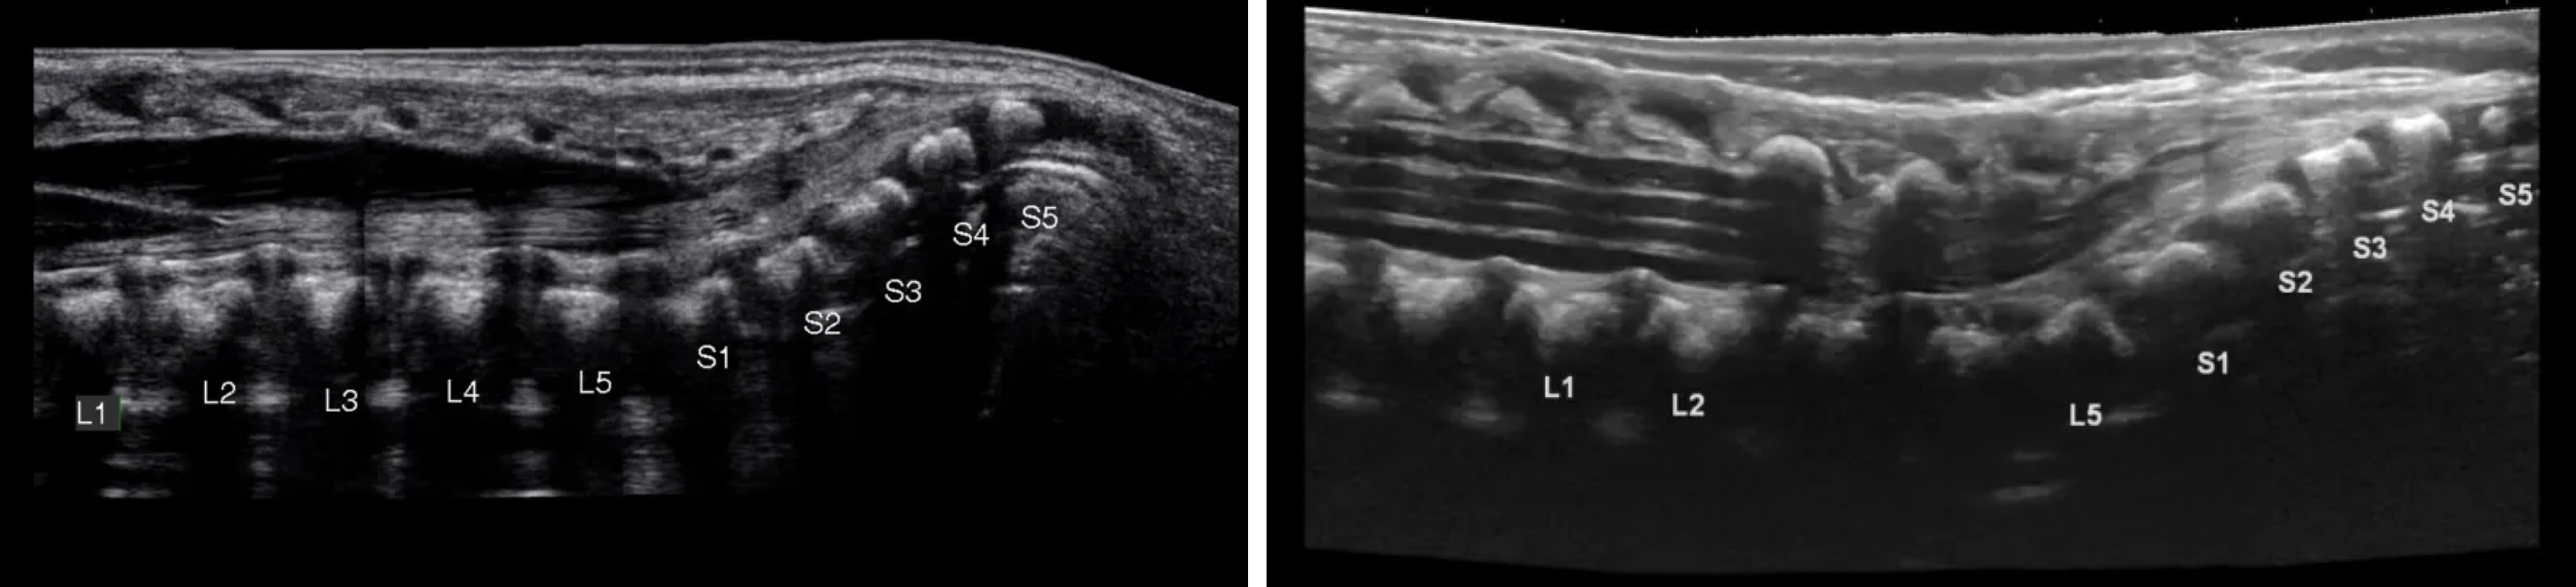

Tethered cord syndrome

정의: 척수 (conus medullaris와 filum terminale)가 비정상적으로 하부 척추 구조물에 고정(tethering)되어, 성장이나 움직임에 따라 척수가 병리적으로 신전(stretching) 되는 상태 → 척수와 신경근에 만성적인 장력이 가해지면서 신경학적 증상이 발생

진단: 영상학적 검사상 conus medullaris의 끝이 비정상적으로 하방에 있는 것을 확인

(정상 위치: L1-L2 level)좌: 정상. conus medullaris의 끝이 L2부근에 위치

우: tethered cord syndrome. conus medullaris 끝이 S1 Rkwl whswo